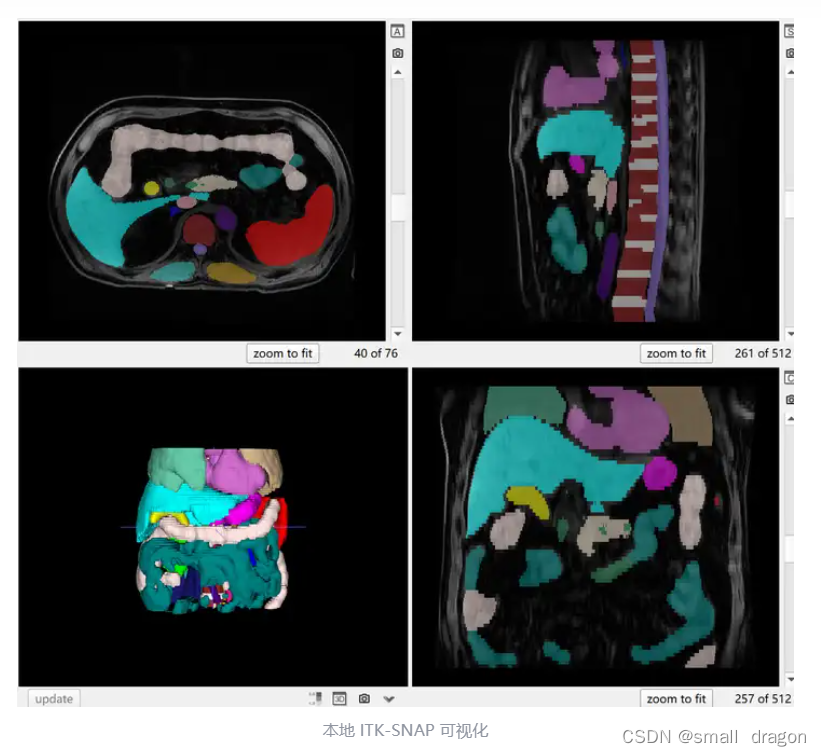

可视化

2、TotalSegmentator MRI

数据集包含了 298 例 MR 图像,并提供多达 56 种不同常用解剖结构的分割标注。其中,251 例 MR 图像来自 2011 年至 2023 年间巴塞尔大学医院的图像存档和通信系统(PACS),另外 47 例 MR 图像来自影像数据共享平台(Imaging Data Commons,IDC),以增加图像的多样性。该数据集源自日常临床工作中的随机抽样,代表了一个可推广到临床应用的真实世界数据集。它涵盖了各种不同的病变、扫描仪、成像序列和来自不同医疗机构的数据。值得注意的是,尽管官方论文提到包含 59 种类别,但公开的数据集中仅提供 56 类标注,略有差异。

磁共振成像(MRI)能够在不使用电离辐射的情况下提供人体详细解剖图像,对于神经系统疾病、肌肉骨骼损伤等多种临床诊断至关重要。尽管 TotalSegmetator (CT) 数据集已被广泛使用,但 MRI 图像分割仍面临挑战,主要是由于不同序列和身体部位的成像参数和协议变化,影响算法的普遍性和准确性。TotalSegmentator MRI 数据集扩展了处理各种 MRI 图像的能力,旨在开发一个开源且易用的分割模型,能够自动且稳健地分割主要解剖结构,而不依赖于具体的 MR 序列。